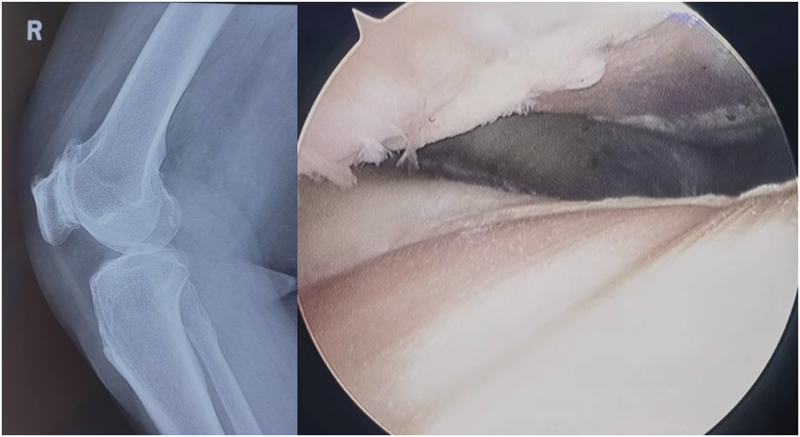

术前X线片显示:正位片胫骨关节间隙良好,轻度骨质增生。侧位片可见髌骨与股骨外髁形成骨磨骨状态,髌上囊有游离体,骨赘产生。

术前X线

外侧入路切开,打开关节囊,术中可见大量骨赘,用咬骨钳去除。骨赘去除后,原来的Wiberg Ⅲ型髌骨恢复变为Wiberg Ⅱ型髌骨。